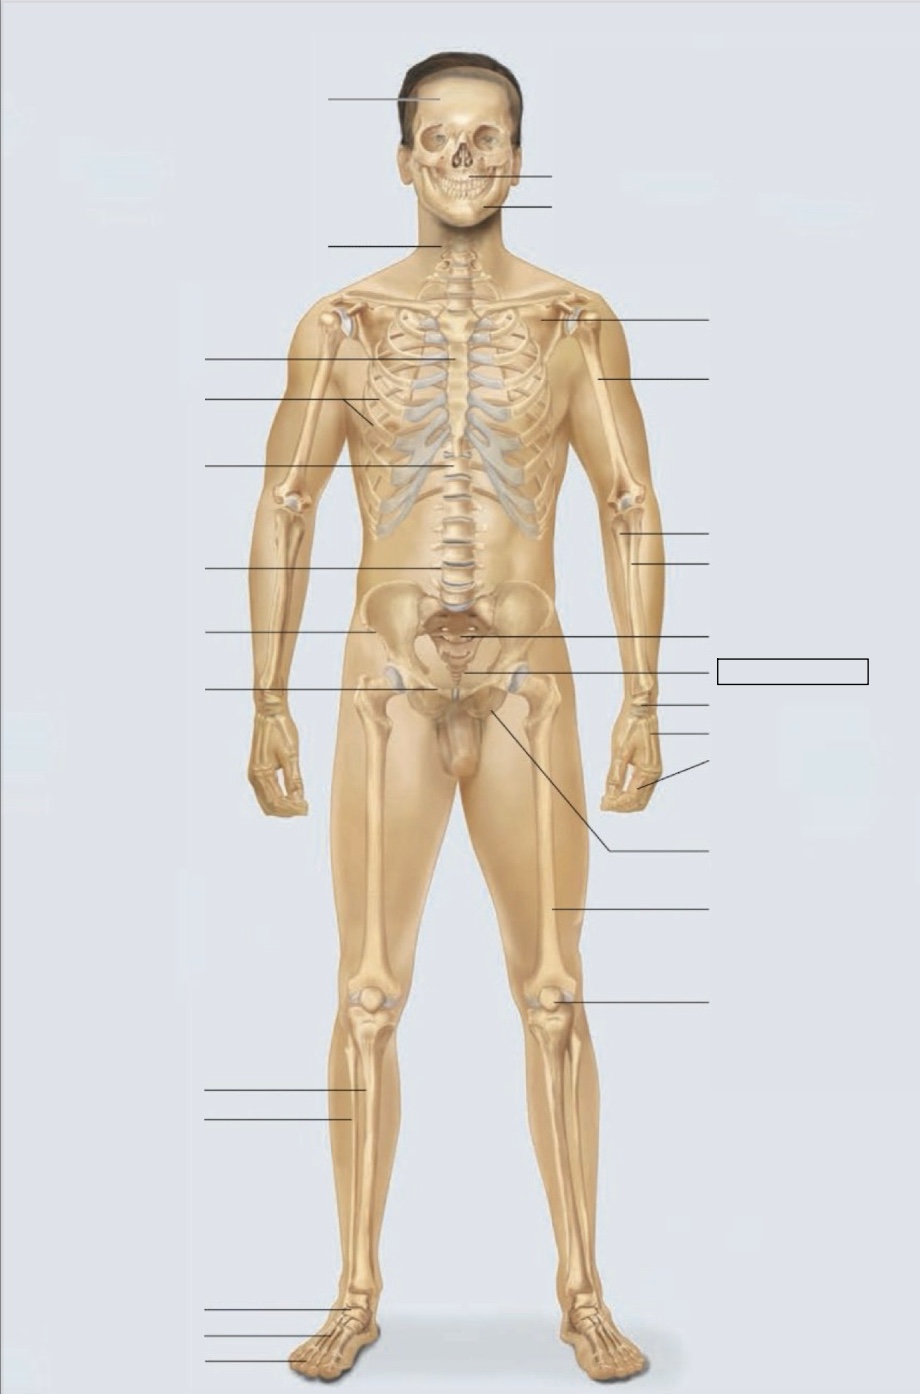

maxilla

mandible

scapula

humerus

ulna

radius

sacrum

coccyx

carpals

metacarpals

phalanges

ischium

femur

patella

phalanges

metatarsals

tarsals

fibula

tibia

pubis

ilium

lumbar vertebrae (L4)

thoracic vertebrae (T11)

ribs

sternum

cervical vertebrae

skull